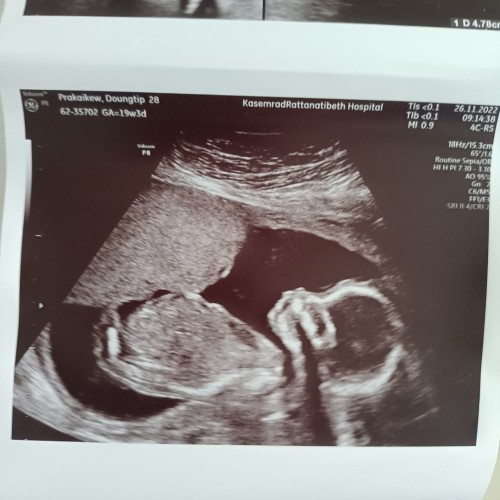

ได้ลูกสาวค่ะ❤️❤️ 19w5d